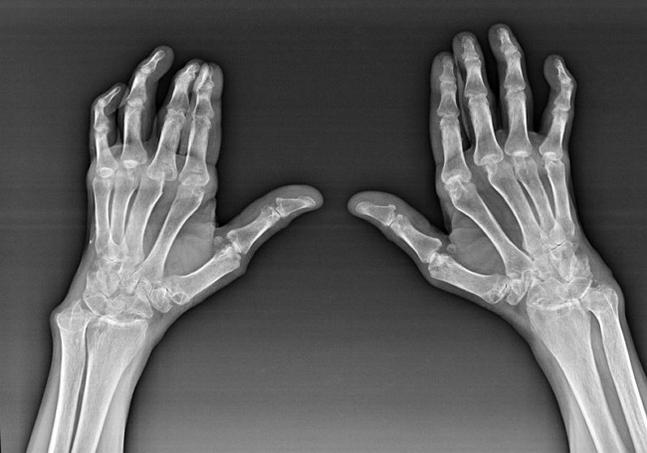

Rheumatoid arthritis is a disease in which the human immune system damages the body's own tissues.In other words, rheumatoid arthritis is an autoimmune pathology.The disease is also systemic because many tissues are affected (Muscles, joints, containers, etc.) and organs (Heart, kidney, lungs, etc.) in the body.

Although rheumatoid arthritis is a systemic disease under it, to a large extent, joints are affected, while lesions in other tissues and organs are in the background.With this disease, almost all types of brush joints can be affected (wrist, carpal tunnel, palm pal-phalanx, interbrain joints).The lesions are usually symmetrical (Those ones.The same joints are affected) hands, accompanied by swelling and joint damage pain.In the morning, during the prosecution in bed, the affected joints have some stiffness that can last about 1 hour and then disappear without traces.

Rheumatoid arthritis often occurs near the affected brush (Piano - Interventricular joints are more frequent) Rheumatoid nodules.They are round strata located below the skin.On brushes, these strata are most commonly found on the back.At palpation, they are dense, inactive, and painless.Their numbers may vary.